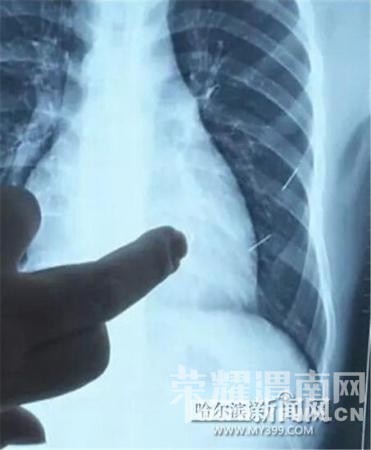

医生指出X光片上的针状物

昨日上午,记者在哈医大二院第八住院部心外三病房找到了躺在病床上痛苦不堪的董立仁,家属正在他身旁不断安慰着他。见记者前来,董立仁母亲李百燕拿出一张X光片,上面可以清晰地看到胸腔内一共有4根针状物,其中一根在心脏部位,两根在胸腔壁上,还有一根在腹腔壁上。

心外三病房董立仁的主治医生告诉记者,董立仁送到医院时病情很危险,随时可能危及生命。“通过检查发现,他心脏内有一个金属异物,正好在心脏上。心脏每次跳动都与其产生摩擦,导致出血,心包积液怀疑是血液。如果大量出血会凝结成血块,血块包裹住心脏就会影响心脏跳动,随时都有停跳的危险。心脏上的异物是致命伤,其余胸腔壁和腹腔壁的异物伤害不大。”

昨天16时30分左右取针手术开始。因钢针随时会危及患者生命,此次手术定义为大型手术。开胸后,医生打开董立仁心包,发现一枚钢针已深深扎入心脏,仅露出1厘米长度在外。拔出钢针后,医生发现,这枚针长达5厘米。受钢针影响,心包出现大量积液,近800毫升。

随后,在下胸壁位置,第二枚钢针顺利取出。在寻找另两枚钢针过程中,普外、胸外多名医生也参与手术,为主刀医生提供更为稳妥的处理建议。根据X光片显示位置,医生未在患者体内找到剩余两枚钢针。医生怀疑,其中一枚钢针可能深藏在肋骨骨膜位置,无法寻找,最后决定结束手术,做进一步观察,研究下一次手术方案。(中国新闻网)